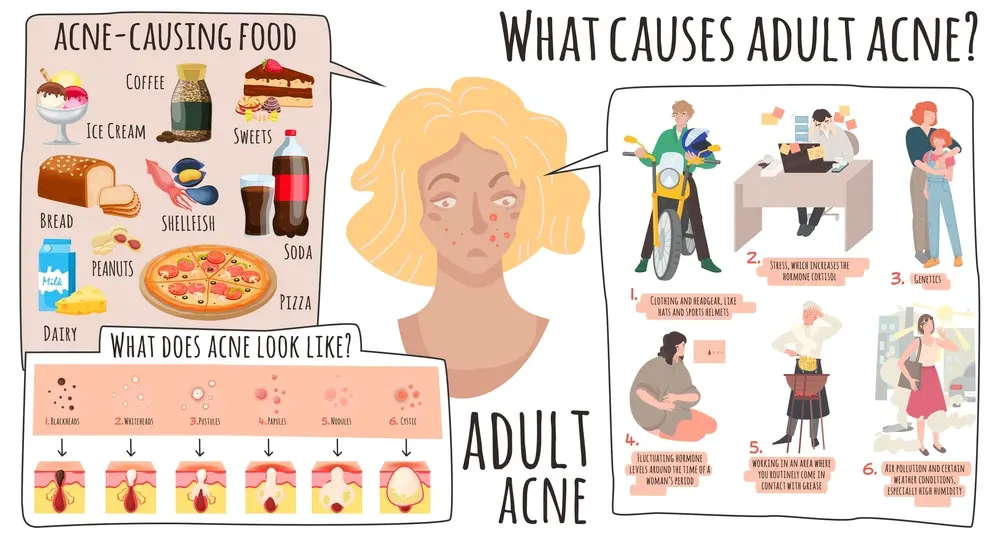

What Causes Adult Acne?

Adult acne is a skin condition that can be caused by a combination of genetics and the environment. Acne can occur at any stage in life, but it is most commonly seen during puberty. Acne can also occur in adults after the age of 30. Adult acne affects both men and women. It can be triggered by hormones, stress, and other factors. It is caused by the overproduction of sebum, which is a naturally occurring oil found on the skin. Acne can occur anywhere on the body, but is most common on the face, neck, and chest. Adult acne usually starts on the face, neck, or chest and can get worse over time. It can be difficult to address, but there are several therapies available that can help reduce the severity and length of the condition.

There is a link between a poor diet and Acne. In fact, a diet high in processed foods and sugar can actually worsen acne. This is because sugary foods promote the overproduction of sebum, which is the oil that helps to breakout your skin. Additionally, diets high in unhealthy fats can also lead to an increase in sebum production. Poor diet can lead to an imbalance of the hormones that control oil production and inflammation, which can trigger acne. Some of the foods that are most commonly linked to acne include processed foods, sugary drinks, and junk food. It’s important to make sure that you’re getting all of the nutrients your body needs to fight acne and keep your skin looking healthy.

Stress

When you’re under a lot of stress, your body starts producing more cortisol, which can cause acne. Cortisol is a hormone that’s responsible for regulating your blood sugar and helping you to fight off infection. It can also play a role in the production of oil and sweat, which can lead to acne. If you have acne and you’re stressed out, there are some things that you can do to reduce your stress levels and improve your acne. First, try to get enough sleep.

Pollution

Pollution can cause Acne. The dirty air can irritate the skin and cause pimples or acne. Pollution can come from cars, factories, or other sources. Cigarette smoke and other types of pollution also can cause Acne. Acne is often caused by hormones and smog, both of which can cause inflammation and rosacea.